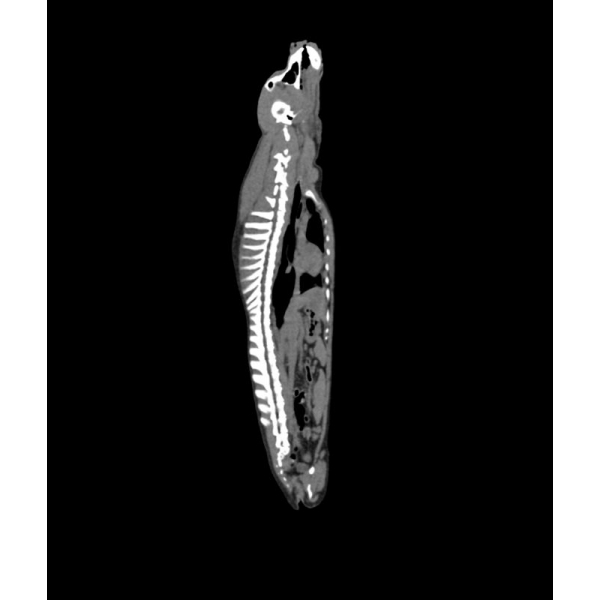

Fantom zagotavlja realistično simulacijo psa brez kontrastnega sredstva. Kosti in mehka tkiva so prikazana verodostojno z realističnimi vrednostmi CT za vsa tkiva pri 120 kVp napetosti cevi v CT. Zračni prostori so zapolnjeni s celuloznim polimernim kompozitom s približno -80 Hounsfieldovimi enotami.

Če se bo fantom uporabljal predvsem pri drugih napetostih cevi (npr. 100 kVp), se lahko po potrebi ustrezno prilagodi kalibracija vrednosti CT ? Fantom zagotavlja tudi realistične kontraste tkiv pri rentgenskem slikanju.

Velikost: 26x15x80 cm